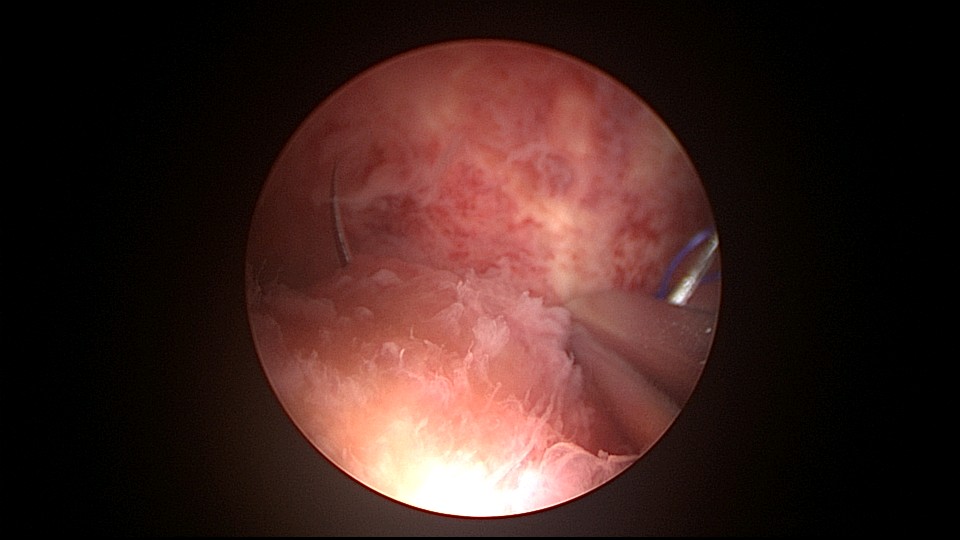

患者38岁,G5P1,剖宫产1次。2023年1月节育环下移带环受孕,宫腔镜取环终止妊娠,同时行左手上臂内侧皮埋避孕,遗憾的是手术医生术中没有找到节育环,术毕复查B超,环仍在宫腔,第二天宫腔镜探查,节育环位于切口憩室内,取出节育环。再次遗憾的是取环后阴道淋漓不净出血,术后第24天复查B超见胚物残留,第三次宫腔镜手术清除残留组织。2025年10月取出皮埋棒,2025年11月外院安环,术后2周复查B超环下移,2025年12月(月经干净3天后),安环医院取出节育环,取环后第6天到我院行宫腔镜安环并做节育环固定。子宫水平位,宫深8.5cm,见切口憩室比宫腔更宽大,形成类似金字塔形状(2次节育环下移原因),行宫腔镜下缝合线结固定节育环,打了3个结,拉过缝合点2个结。第十七例节育环固定。既往带环受孕,多次宫腔镜手术。术后2周复查B超,节育环位置正常,环顶端距宫底1.6cm。